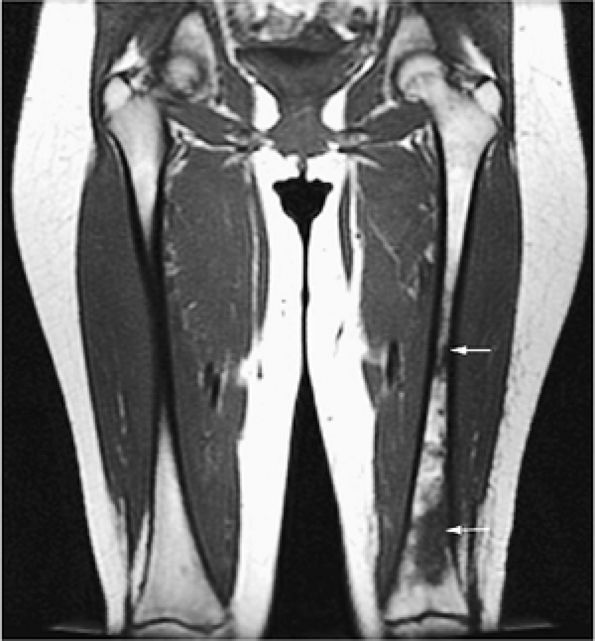

|

FIGURE 13.12 ● Abnormal low-signal-intensity marrow of the bilateral lower extremities due to leukemic infiltration, seen on a coronal T1-weighted image. Note extension of leukemic infiltrates into the epiphyses.